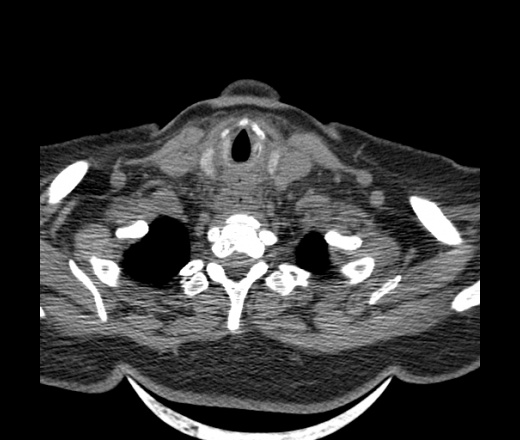

Женщина поступила в х/о спустя 4 дня после того как при употреблении карася подавилась костью.

Наличие газа в средостении на протяжении тел С2-С6 (медиастинальна эмфизема); рыбная кость на уровне тела С6.

При всем уважении, но говорить о медиастинальной эмфиземе, оценивая мягкие ткани шеи, как-то слишком резко. На мой взгляд, это ретрофарингеальное пространство.

Эвакуировали почти 100мл гноя. Но кость не смогли найти. Думаю что она даст дальнейшее ослоднение. Эндоскопически за черпалонадгортаной звязкой не смогли зайти в пищевод, все мягкие ткани отечные, просвет пищевода сдавлен. По всей видимости параэзофагеальная клетчака тоже задействована. Эмпиема, если ее можно так назвать, незнаю как правильно дошла до уровня яремной вырезки. Чем закончиться напишу. Ждем медиастинита.

Флегмона заглоточного пространства шеи, только операция, флегмоны вскрывают. Риск медиастинита.

Согласен с Вами; конечно, наличие газа в клетчатке ретрофарингеального пространства (затмение с опечаткой..). К сожалению, процесс "продвигается" к медиастиниту. Но почему никто, не отмечает наличие рыб. кости; или это для Всех очевидно?

Кость то мы сразу выявили, размеры где то 17*2мм, но ее так и не получается найти в этой каше